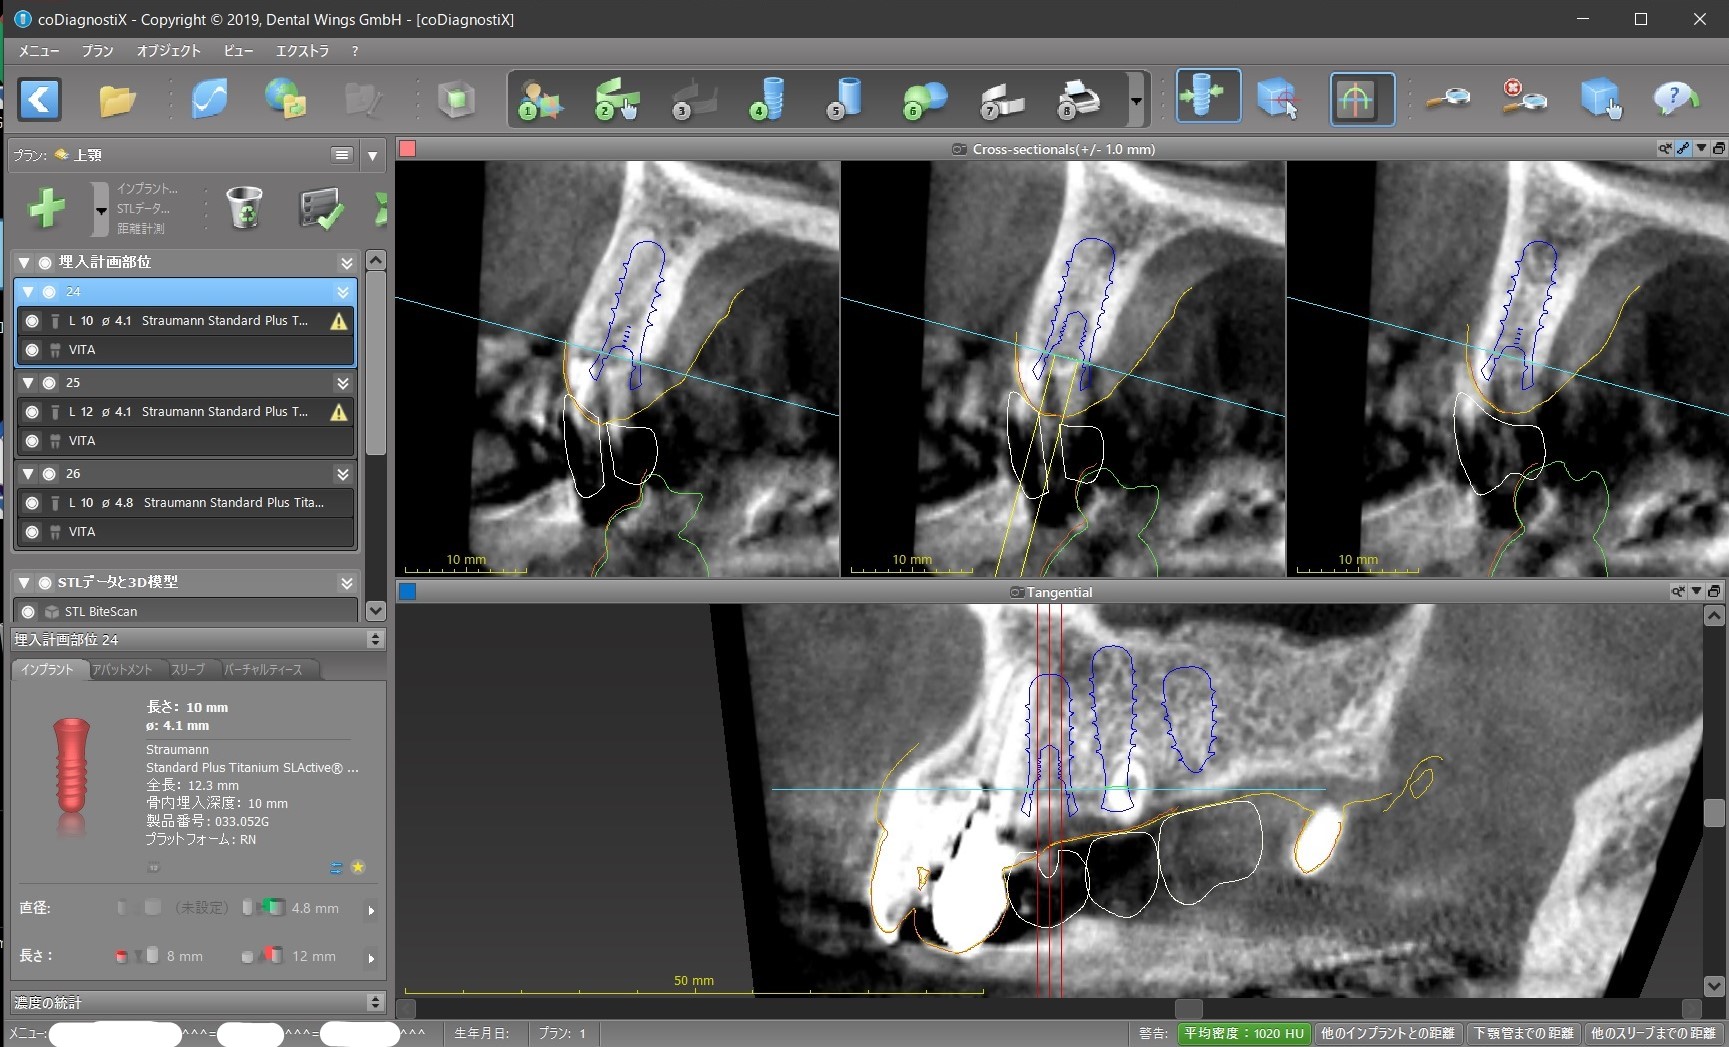

今回で言えば、インプラントを前から順に#24、#25、#26と呼ぶと

① #24がその前の天然歯に当たって、そもそもこの位置に入れられない。

② 前述のように#24上部構造が下の歯と咬まない。ちゃんと咬むようにするためには矯正治療が必要になる。

③ #24のインプラントと上部構造との間に角度を付けるか、もしくはGBR(骨を増やす、作る処置)が必要になる。

④ #25インプラント部位に歯の根が残っているので、これをインプラント手術の時に取り除くのと同時にそこに骨を増やす処置が必要になる。